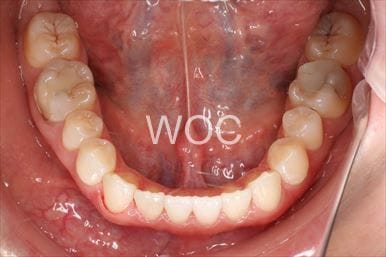

治療後2

- 年齢:20歳女性

- 主訴:出っ歯が気になる

- 基本矯正料金:120万円

- 治療期間:1年7ヶ月

- 抜歯部位:上顎両側第一小臼歯